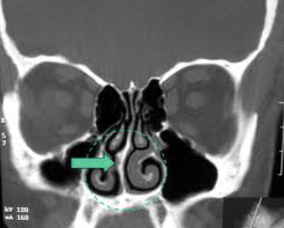

IMAGEN DE OCUPACIÓN PARCIAL EN SENO MAXILAR DERECHO DE UN 30% DE OCUPACIÓN. PERIFERICO, MARGINAL. CONDESVIACIÓN SEPTAL A LA DERECHA DE CONFORMACIÓN ÓSEA (PORQUE SE VE BLANCO)

SE OBSERVA HIPERTROFIA DE CORNETE INFERIOR IZQUIERDO. SUPERFICIE FESTONEADA: DEGENERACIÓN PÓLIPOIDEA.

CONCLUSIÓN: SINUSITIS MAXILOETMOIDAL BL, DESVIACIÓN SEPTAL E HIPERTROFIA DE CORNETE INFERIOR IZQUIERDO CON DEGENERACIÓN POLIPOIDEA.